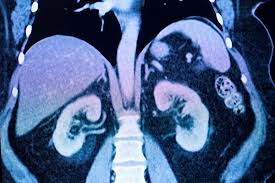

Contrast Induced Nephropathy

<br /><br />CIN is defined as an elevation of serum creatinine (Scr) of more than 25% or ≥0.5 mg/dl (44 μmol/l) from baseline within 48 h after excluding other factors that may cause nephropathy, such as nephrotoxins, hypotension, urinary obstruction, or atheromatous emboli. It is self-limited in most instances, with Scr levels peaking in 3-5 days and gradually returning to baseline levels within 7-10 days.<br />Prevalence <br />CIN is one of the major causes of hospital-acquired acute kidney injury (AKI) and represents about 12% of the cases. It is the third most common cause after renal hypoperfusion (42%) and postoperative renal injury (18%).<br />The reported incidence of CIN after percutaneous coronary intervention (PCI) varies between 0 and 24%, depending on the prevalence of associated risk factors, with the higher incidence being reported after emergency PCI.<br />A meta-analysis that included 40 studies, found a 6% incidence of CIN after contrast enhanced computed tomography (CT), 9% after peripheral angiography, and 4% after intravenous pyelography.<br />The incidence of CIN is low in patients with normal renal function (0-5%).However, several prospective controlled trials reported an incidence of 12-27% in patients with preexisting renal impairment. Furthermore, in one study, an incidence as high as 50% was reported in patients with diabetic nephropathy undergoing coronary angiography in spite of the use of low-osmolar CM (LOCM) and adequate hydration. Notably, up to 15% of them required dialysis. Development of CIN is associated with a longer hospital stay, an increased morbidity and mortality, in addition to a higher cost.<br />Pathophysiology<br />Although the definite mechanism of CIN is not well-understood, several mechanisms have been proposed<br />• Renal medullary hypoxia due to either a decrease in vasodilators (nitric oxide or prostaglandins), or an increase in vasoconstrictors (adenosine and endothelin).<br />• Direct toxicity of CM which could be related to harmful effects of free radicals and oxidative stress. It is thought that activation of cytokine-induced inflammatory mediators by reactive free radicals is the responsible mechanism. Conversely, the inhibition or reduction of free radicals formation might reduce CIN by alkalinizing tubular cells.<br />• In addition, apoptosis may also play a role in the development of CIN<br />Risk factors<br />Multiple risk factors may contribute to the development of CIN; these factors are divided into two groups; patient- and procedure-related.<br />Preexisting renal insufficiency (estimated glomerular filtration rate (eGFR) <60 ml/min) and diabetes mellitus are the most important patient-related risk factors. Others, include age >75 years, uncontrolled hypertension, hypotension requiring inotropes, congestive heart failure (CHF), use of intra-aortic balloon pump (IABP), anemia, hypoalbuminemia, and liver cirrhosis.<br />Procedure-related factors include high contrast volume, osmolality or viscosity, and repeated exposures to CM within 72 h. Other factors that may increase the risk of CIN include the concomitant use of diuretics or nephrotoxic drugs (nonsteroidal anti-inflammatory drugs (NSAIDs) and aminoglycosides). <br /><br />Treatment<br />There is no definitive treatment available for established CIN; therefore, the benefit for CM-based diagnostic studies or interventional procedures should always be weighed against the risk of CIN. In addition, repeated exposure to CM within a short period of time should be avoided whenever possible.<br />Prevention strategies<br />Several pharmacological and nonpharmacological approaches have been evaluated for the prevention of CIN. The prevention strategies are most important in patients at high risk for CIN, such as those with AKI or preexisting chronic kidney disease (CKD). It is well established that minimizing the volume of CM, preventing volume depletion and avoiding activation of renal vasoconstriction are the most effective measures to prevent CIN. In addition, the concomitant use of diuretics or nephrotoxins (e.g. nonsteroidal anti-inflammatory drugs (NSAIDs), cytotoxic drugs, and aminoglycosides) should be avoided<br />